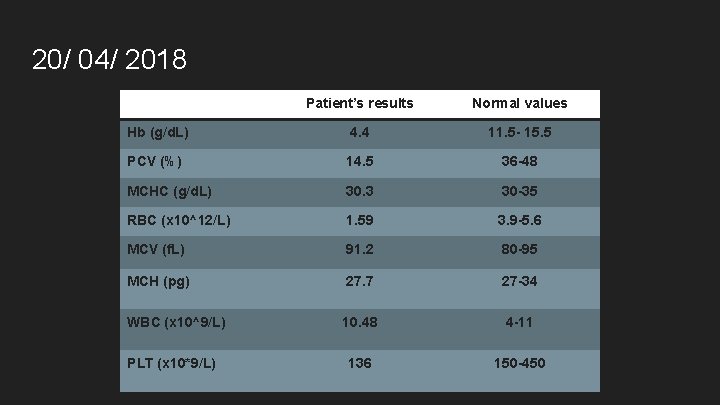

20/ 04/ 2018 Patient’s results Normal values Hb (g/d. L) 4. 4 11. 5 - 15. 5 PCV (%) 14. 5 36 -48 MCHC (g/d. L) 30. 3 30 -35 RBC (x 10^12/L) 1. 59 3. 9 -5. 6 MCV (f. L) 91. 2 80 -95 MCH (pg) 27. 7 27 -34 WBC (x 10^9/L) 10. 48 4 -11 136 150 -450 PLT (x 10*9/L)